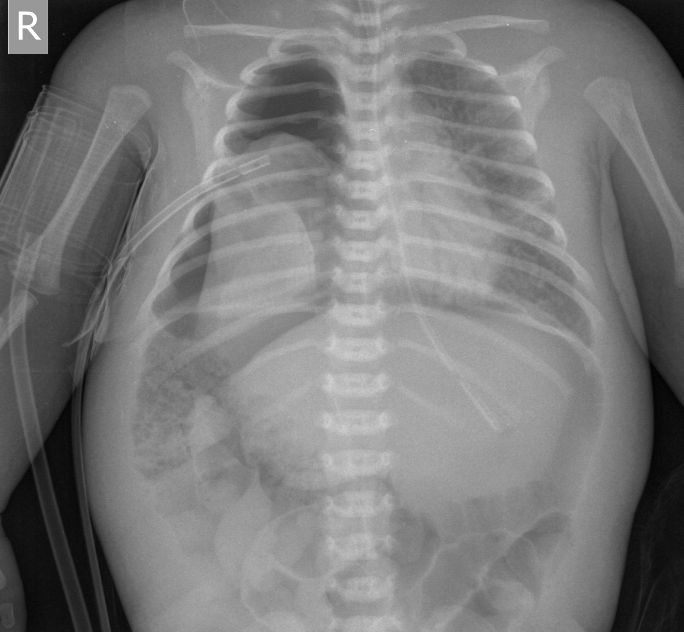

Ребёнок с рождения находится в РАО новорожденных, причину пока не скажу. На момент снимка - возраст 1 месяц. Снимок сделан в связи с резким ухудшением состояния, падением сатурации.